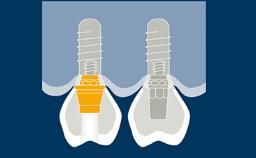

Implants and their prostheses replace teeth.

They therefore have to participate fully in oral function. A substantial part of oral function is related to occlusion when the teeth and their replacements make contact.

This module will examine the ability of implants and their prostheses to withstand occlusal forces and offer guidelines for occlusal design.